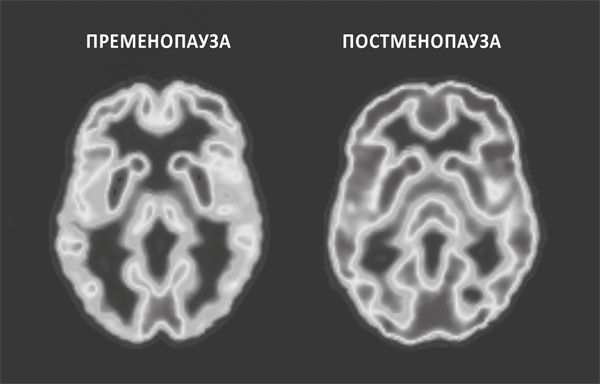

Это хорошо видно на приведенных ниже снимках со сканера. Слева показана метаболическая активность мозга женщины, еще не имеющей признаков менопаузы, т. е. на этапе пременопаузы. На правом снимке мозг женщины в постменопаузе. Насыщенность серого оттенка отражает степень активности: чем темнее, тем ниже. Снимок мозга в постменопаузе в целом выглядит темнее, а это значит, что его метаболические процессы протекают значительно менее активно, чем в пременопаузе. И это не единичный случай. Снимок, можно сказать, «усредненный». По нашим наблюдениям, в некоторых случаях уровень активности мозга снижается на целых 30 %. Тревожно, что такие же результаты были замечены у женщин уже незадолго до наступления менопаузы. А вот у мужчин того же возраста отмечались минимальные изменения, а во многих случаях вообще никаких.

РИСУНОК 1. МЕНОПАУЗА: АКТИВНОСТЬ МОЗГА ДО И ПОСЛЕ